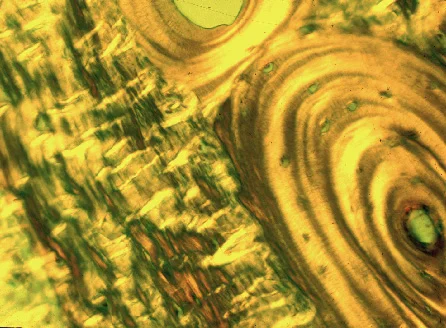

Doutor Maurício Araújo é a maior referência brasileira no cenário mundial em Periodontia e Implantodontia. Sua relevância é reflexo de um trabalho revolucionário sobre a cicatrização dos tecidos bucais, que mudou profundamente a maneira como os dentistas lidam com cirurgias de implantes e de enxerto de tecidos.

Araújo é um dentista referência no cenário odontológico internacional. Conhecido e ao redor do mundo pela sua capacidade de transmitir conhecimentos sólidos e baseados em evidências científicas. Reconhecido pelos pacientes por sua odontologia eficiente, de qualidade e humanizada.